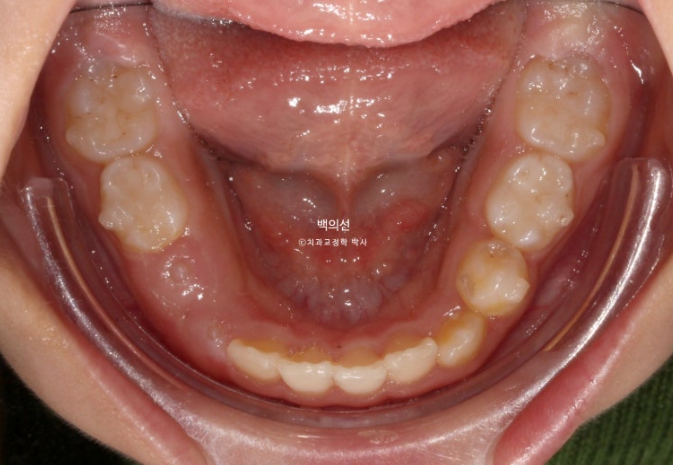

교정치료를 위해 온 만 9세 어린이입니다.

부모님이 고치고 싶은 것은 앞니가 깊게 물리는 과개교합

아래 앞니가 보이지 않을 정도의 심한 과개교합입니다.

앞니 돌출이 있으며

악궁전반부가 좁습니다.

아래도 마찬가지로 악궁확장이 필요합니다.

이 날 공간이 부족하여 앞니가 삐뚤게 나왔고 곧 나올 송곳니는 공간이 부족하여 덧니로 나올 상황입니다.